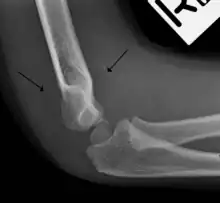

Fat pad sign

The fat pad sign, also known as the sail sign, is a potential finding on elbow radiography which suggests a fracture of one or more bones at the elbow. It is may indicate an occult fracture that is not directly visible. Its name derives from the fact that it has the shape of a spinnaker (sail).[1] It is caused by displacement of the fat pad around the elbow joint. Both anterior and posterior fat pad signs exist, and both can be found on the same X-ray.

In addition to fracture, any process resulting in an elbow joint effusion may also demonstrate an abnormal fat pad sign. Increased intracapsular fluid is also seen in several conditions other than fracture and this produces the abnormal fat pad sign. (toxic synovitis, septic arthritis, Juvenile Rheumatoid Arthritis, osteomyelitis of the distal humeral physis and secondary septic joint). In these instances, history and clinical examination in addition laboratory results (WBC, ESR, CRP) will guide the provider in determining whether to treat the condition as an occult fracture or continue workup for other pathology.

The fat pad sign is invaluable in assessing for the presence of an intra-articular fracture of the elbow. An anterior fat pad is often normal. However a posterior fat pad seen on a lateral x-ray of the elbow is always abnormal. The patient will be unable to flex their elbow and requires orthopaedic input.[2]

The posterior fat pad is normally pressed in the olecranon fossa by the triceps tendon, and hence invisible on lateral radiograph of the elbow.[3] When there is a fracture of the distal humerus, or other pathology involving the elbow joint, inflammation develops around the synovial membrane forcing the fat pad out of its normal physiologic resting place. This is visible as the "posterior fat pad sign" and is often the only visible marker of a fracture, particularly in the pediatrics population.